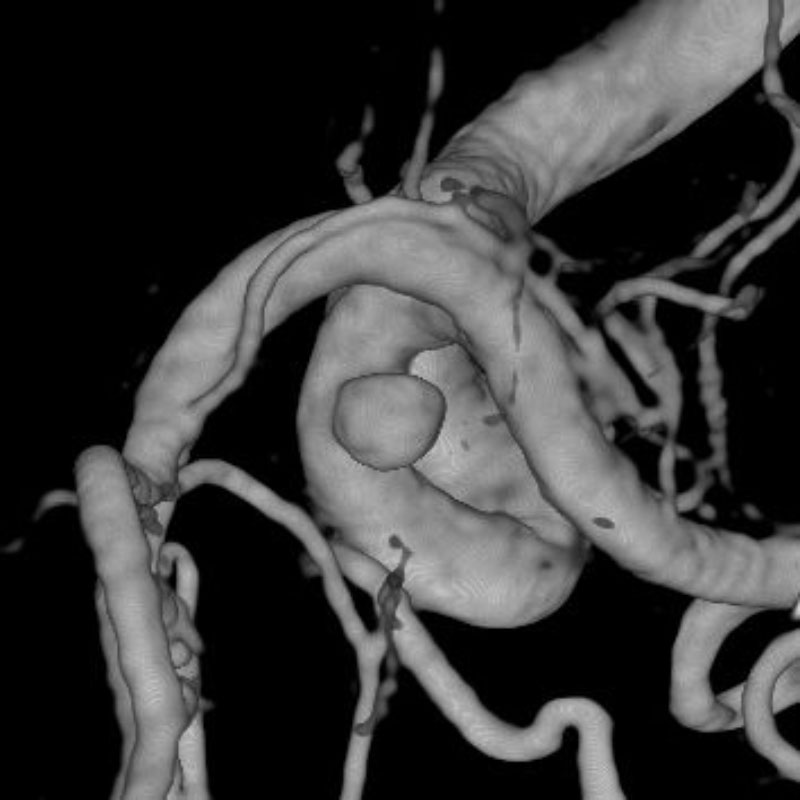

脳動静脈奇形

血管塞栓術

松田/濵田/元永